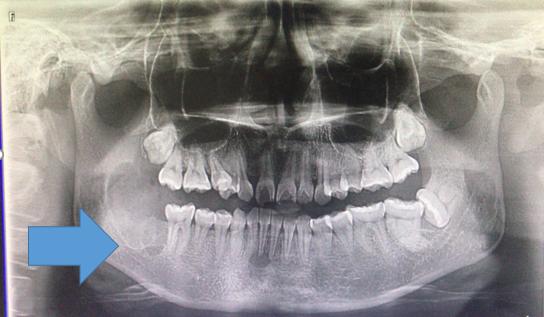

起因:患者于当地诊所拔除右下第二磨牙,拔牙后创口长时间未愈合,经常流出有异味的液体。拍摄口腔全景片示:拔牙窝空虚,右下颌骨发现很大的黑洞。

右下颌骨囊肿

治疗设计:A: 1、患者年轻女性,口腔卫生情况可;2、易沟通,医从性较好;3、患者希望尽快修复缺牙。B:1、病灶范围确切且较局限;2、骨质膨隆不明显;3、具备手术指征。经与患者及家属积极沟通后,采取手术方式:右下颌骨囊肿刮治+同期异体骨植入